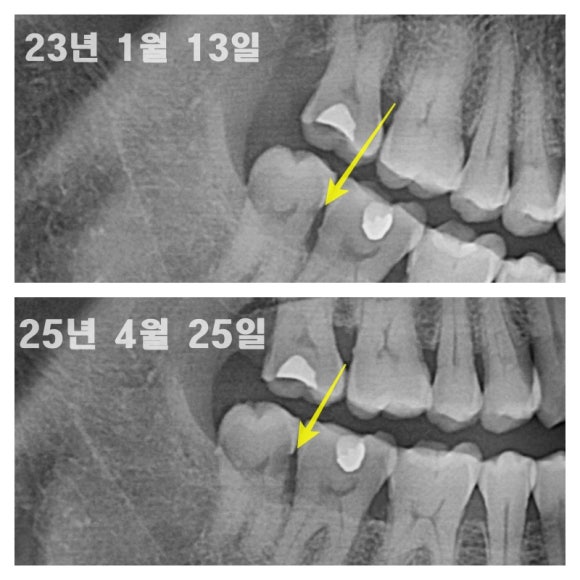

2. 충치치료 시기 놓쳐서 단순 때우는 치료로 가능했던 충치를 신경치료를 해야만 했던 케이스

충치가 작을 때 얼른 치료했으면 간단한 때우기 치료로 치료가 가능했을 텐데, 치료를 미루시다가 결국 통증으로 내원하셨고

때우기가 아닌 신경치료 후 씌우기로 치료를 하셨습니다.

치아 비용은 두 배, 자연치아 삭제량(치아 손실량) 세배, 치료시간 및 기간은 네 배가 소요되었어요.